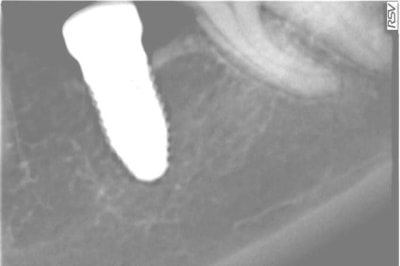

Je vous joins un cas qui m'a été adressé il y a deux ans à peu près pour une cratérisation (double). J'ai juste observé, d'autant que je n'étais pas le poseur. La radiographie de cette année était identique. La patiente n'a aucune symptomatologie. Je continue à surveiller.

PS : à noter également l'image au niveau du sinus. Pas d'évolution également depuis deux ans. La patiente m'a raconté avoir ressenti un "pic" lors de la pose.

Dommage Digit que ta radio ne soit pas dans le plan des spires.

sinon ta radio confirme mes propos

J'ai les radios préop et post op.

La rétro n'est vraiment pas terrible, mais depuis juin ça a quand même sacrément évolué.

Qu'en pensez-vous?

> AVANT

> APRES

> De mai à novembre

tu as perdu 1 ou 2 spires, vu la qualité de la première radio, difficile à dire.

La seconde radio est très contrastée par rapport à la première.